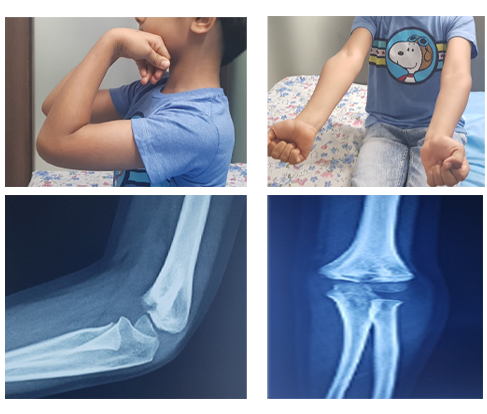

Elbow Fracture

Before

Swelling, Pain, Bruises and inability to move the elbow

After

Treatment may vary from as simple as sling application to an urgent surgery depending upon the severity of fracture